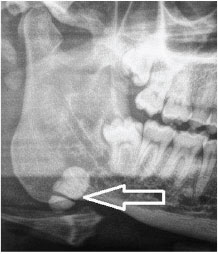

2. What condition can be seen in the following X ray? ( Open arrow)